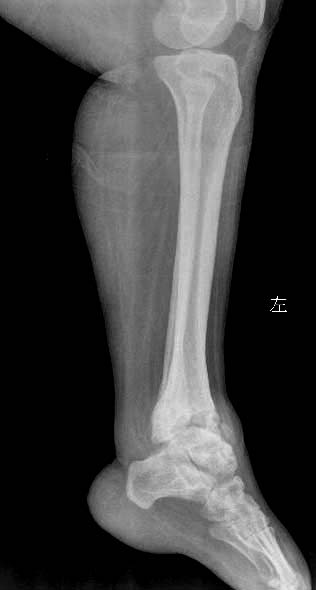

女.29岁.先天髋关节脱位.腰椎后部向外膨出.外院诊断骨肉瘤.我院诊断夏科氏关节病。

该患者有脊柱裂和右侧髋臼发育不良,踝关节改变符合神经性骨关节病,必要时结合临床排除结核.

支持:1、脊柱裂;

2、右侧髋臼发育不良伴半脱位;

3、双踝关节夏科氏关节病。

1,双踝夏科氏关节;

2,右侧扁平髋并右髋关节半脱位;

3,脊柱裂.

x1147手术病理双踝夏科氏关节病、右下肢骨髓炎瘘道形成感染截肢!

踝关节表现好像是夏科氏关节病